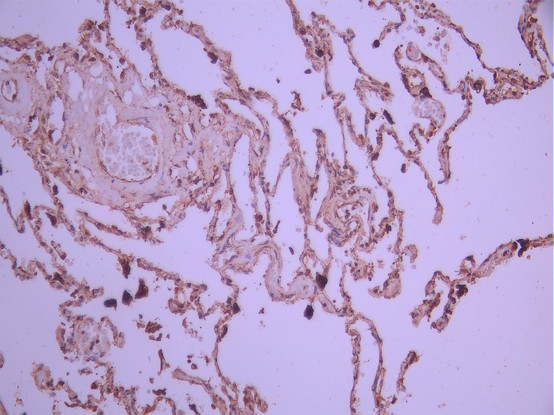

IHC image of CSB-RA055227A0HU diluted at 1:100 and staining in paraffin-embedded human lung tissue performed on a Leica BondTM system. After dewaxing and hydration, antigen retrieval was mediated by high pressure in a citrate buffer (pH 6.0). Section was blocked with 10% normal goat serum 30min at RT. Then primary antibody (1% BSA) was incubated at 4°C overnight. The primary is detected by a Goat anti-rabbit polymer IgG labeled by HRP and visualized using 0.05% DAB.